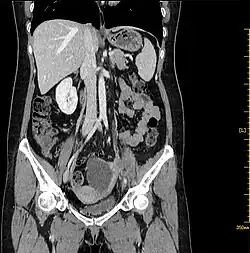

Abdominal CT shows a 7.1 × 4.3 × 5.4 cm septal cystic, solid mass was detected on the left adnexal, and the solid components were enhanced.